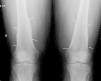

The patient, a 45-year-old male, was referred to the rheumatology clinic due to diffuse joint pain on the wrists and knees. The patient was diagnosed with liver cirrhosis and severe hepatopulmonary syndrome. Physical examination showed swelling of the knees and wrists (arthritis) and clubbing. The X-rays requested showed periosteal thickening observed continuously, in a diaphysometaphysiary location of the radius and ulna in both forearms, and predominantly in distal femurs and both knees, compatible with nonaggressive periosteal reaction. Fig. 1 shows periosteal thickening affecting both femurs on the concave bone edge and respecting the epiphysis, and equal involvement of the radius and ulna on the right wrist, in Fig. 2.

The findings on physical examination were finger-clubbing and arthritis of the hands and knees, and the radiological presence of continuous noninvasive periostitis of the concave edge affecting the long bones of both the upper and lower extremities, with a diagnosis of hypertrophic osteoarthropathy. This clinical entity is mainly associated with intrathoracic processes (especially malignancy, namely lung cancer and pleural tumors), but also other diseases among which one can include liver disease (hepatocellular carcinoma, alcoholic hepatitis and both Portal biliary cirrhosis and cirrhosis of the liver).1–3